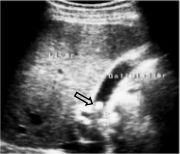

Picture1.

Echogenic

focus

in

the

gallbladder

lumen.